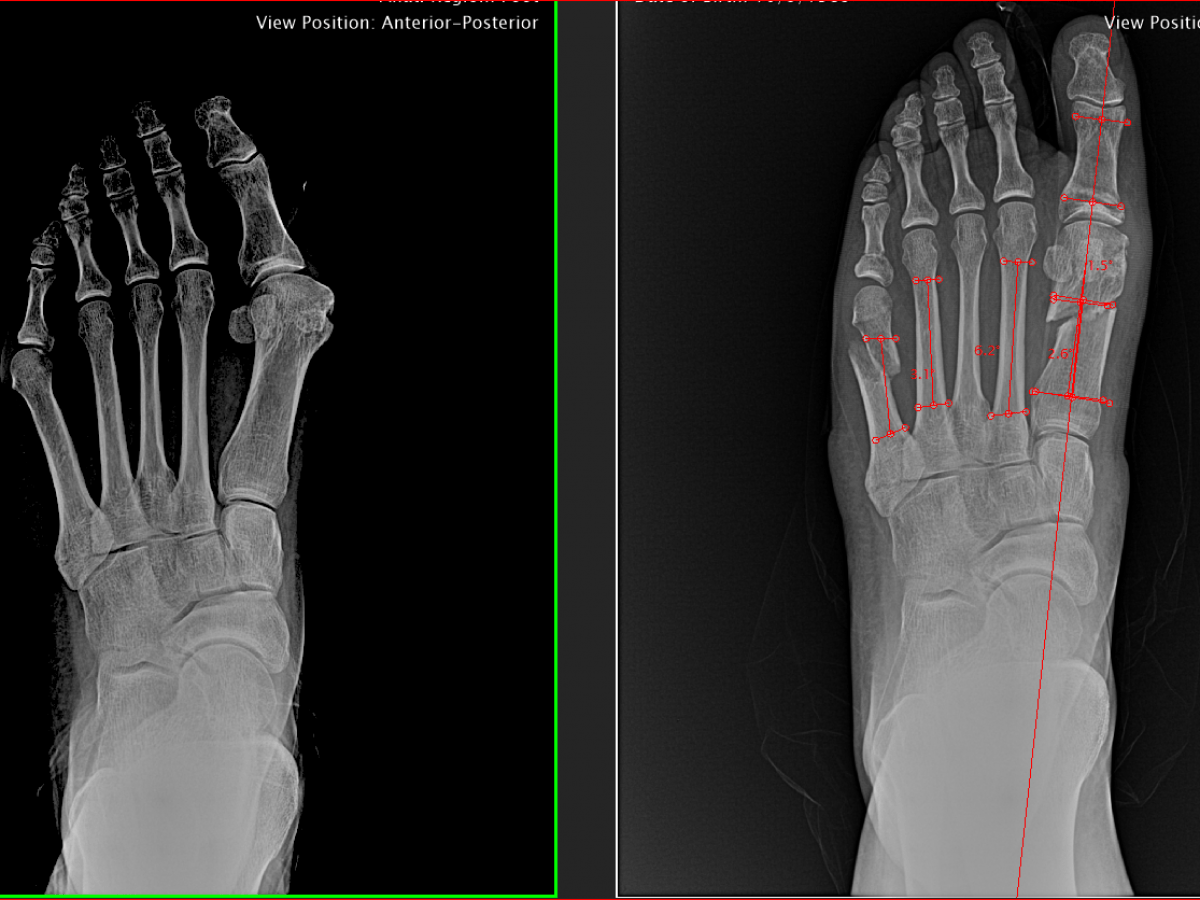

My bunion correction surgery pre and post op xrays r/pics Post Bunion Surgery X Rays Halluces valgi) is a fixed abduction of the first metatarsophalangeal joint of the great toe. The big toe drifts closer to the other toes, and the metatarsal bone sticks out further. Bunion a hallux valgus (plural: Learn about what a bunion is, reasons for surgery, the different types of bunion surgery and risks, and what to expect before, during, and. Post Bunion Surgery X Rays.

Before & After xrays double bunionectomy on 1st & 5th toes, double Post Bunion Surgery X Rays You will also need to see your primary care provider for tests to make sure that it would be safe for you to have surgery. Learn about what a bunion is, reasons for surgery, the different types of bunion surgery and risks, and what to expect before, during, and after surgery. A bunionette, also known as a tailor's bunion, metatarsus. Post Bunion Surgery X Rays.